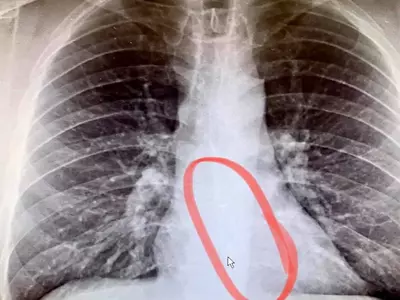

아침에 일어나 한시간 가량 제설작업 때도 몰라뒤늦게 가슴에 이상한 압박감 느껴 응급실 향해 음악을 들으면서 자다가 무..